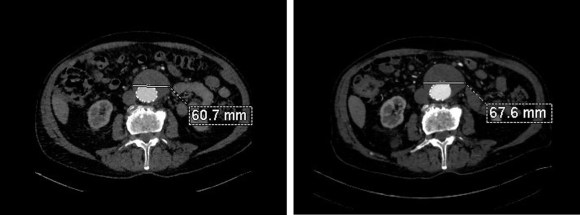

The patient had undergone an uneventful EVAR, but in followup had developed AAA sac growth. Pictured above are the post deployment CT’s from 1 month and 6 months. Reviewing the original aortogram, you can see that there was flow into the sac very late via an iliolumbar collateral.

Plan was made for arteriography and intervention. As discussed in an earlier post, 3D VR was very helpful in planning access to the type II endoleak, particularly in plotting C-arm angles and access vessels.